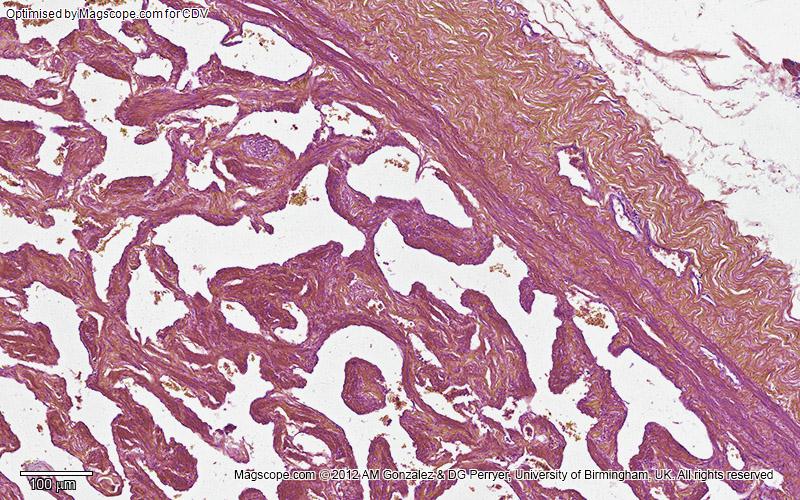

Low magnification image of a cross section of the corpus spongiosum and tunica albuginea of the human penis

Disability awareness and educational equity: This image has been optimised for red-green colour blind observers who are often unable to differentiate the colours in histological slides, using methods described by Professors Landini and Perryer here.